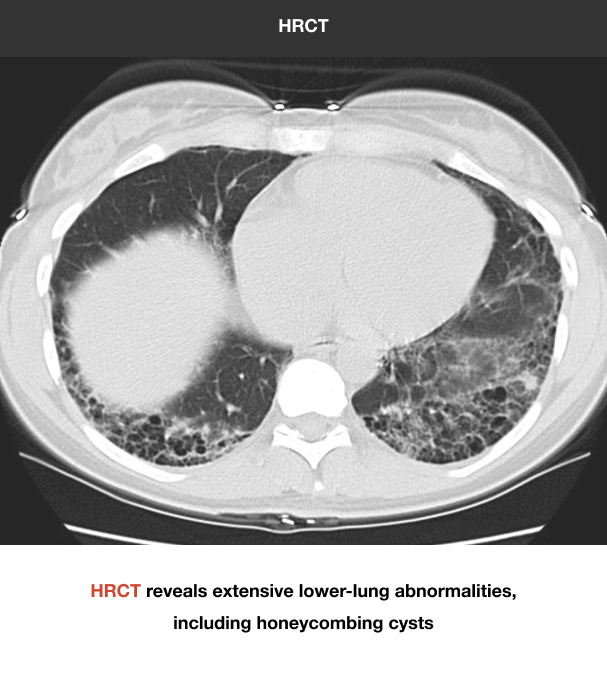

HRCT is the standard in diagnosing ILD9

HRCT allows for the recognition of fibrosis and other abnormalities that may not be apparent on chest x-ray. Below is a comparison of imaging from a 43-year-old female with 3 weeks of sinus congestion and clear sputum production after running:

Recognizing pulmonary fibrosis early on HRCT is critical18-20

When ILD is suspected in the primary care setting, consider follow-up evaluation by a pulmonologist. Early referral can enable early access to HRCT and multidisciplinary evaluation, the key to early and accurate diagnosis of fibrotic ILDs.